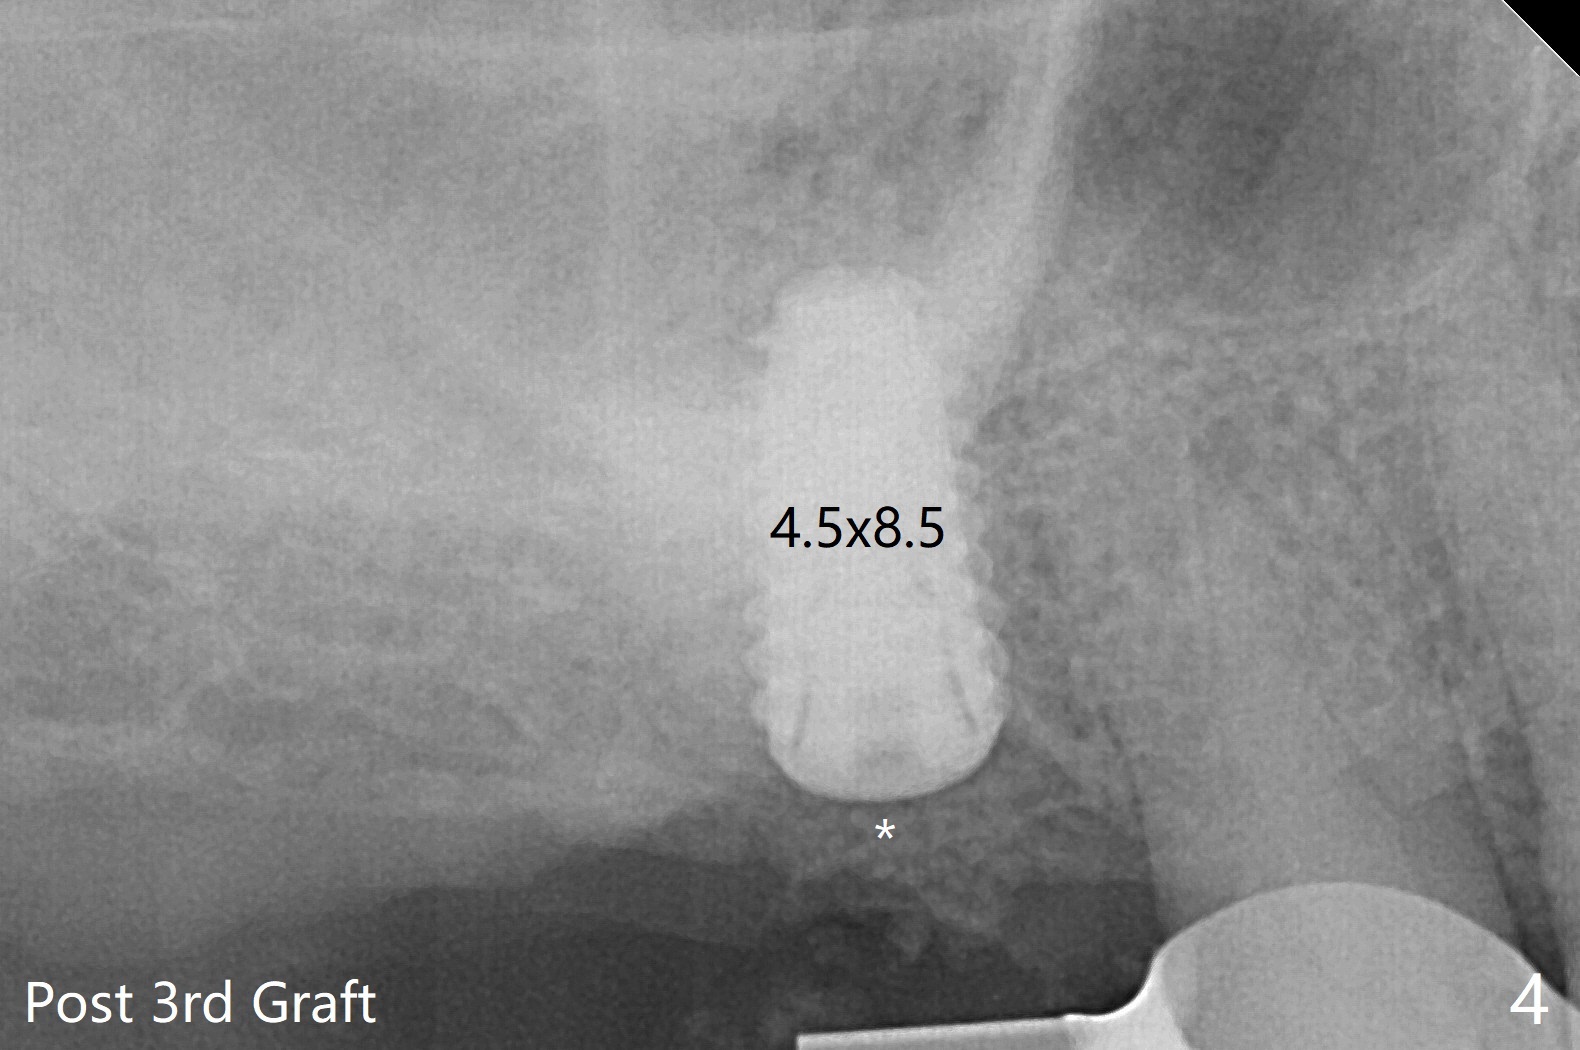

在导板协助下,顺利完成右上6钻洞,用圆钻穿过上颌窦底板,然后使用粘性骨粉(之前半张PRF膜)和4乘10毫米报废植体做第一次(图一,二),第二次(图三),第三次(图四,五)提升,退出报废植体后,拧入正式植体(4.5乘8.5毫米)。由于扭力大约10Ncm,放置愈合螺帽。植体颊侧骨壁比较低,螺帽上放置骨粉(图四,五:*),后者太多,再没有空间放置PRF膜,只好放置在骨粉表面,容易滑动,所以需要安置间隙保持器(图四,五)。在拍摄根尖片时,PRF膜丢失,只好在骨粉表面放置Teflon,然后放置牙周敷料,借助保持器固定。术后两周牙周敷料脱落,而间隙保持器仍在,下面牙龈基本愈合(图六,7)。今后使用导板做上颌窦提升,种植,最好使用导板的环形刀在牙龈上轻轻做过标记,然后用Biopsy Punch完整切除牙龈,放置于PRF上清液备用。如果植体扭力低,放置骨粉后,覆盖切除的牙龈,牙周胶水固定。